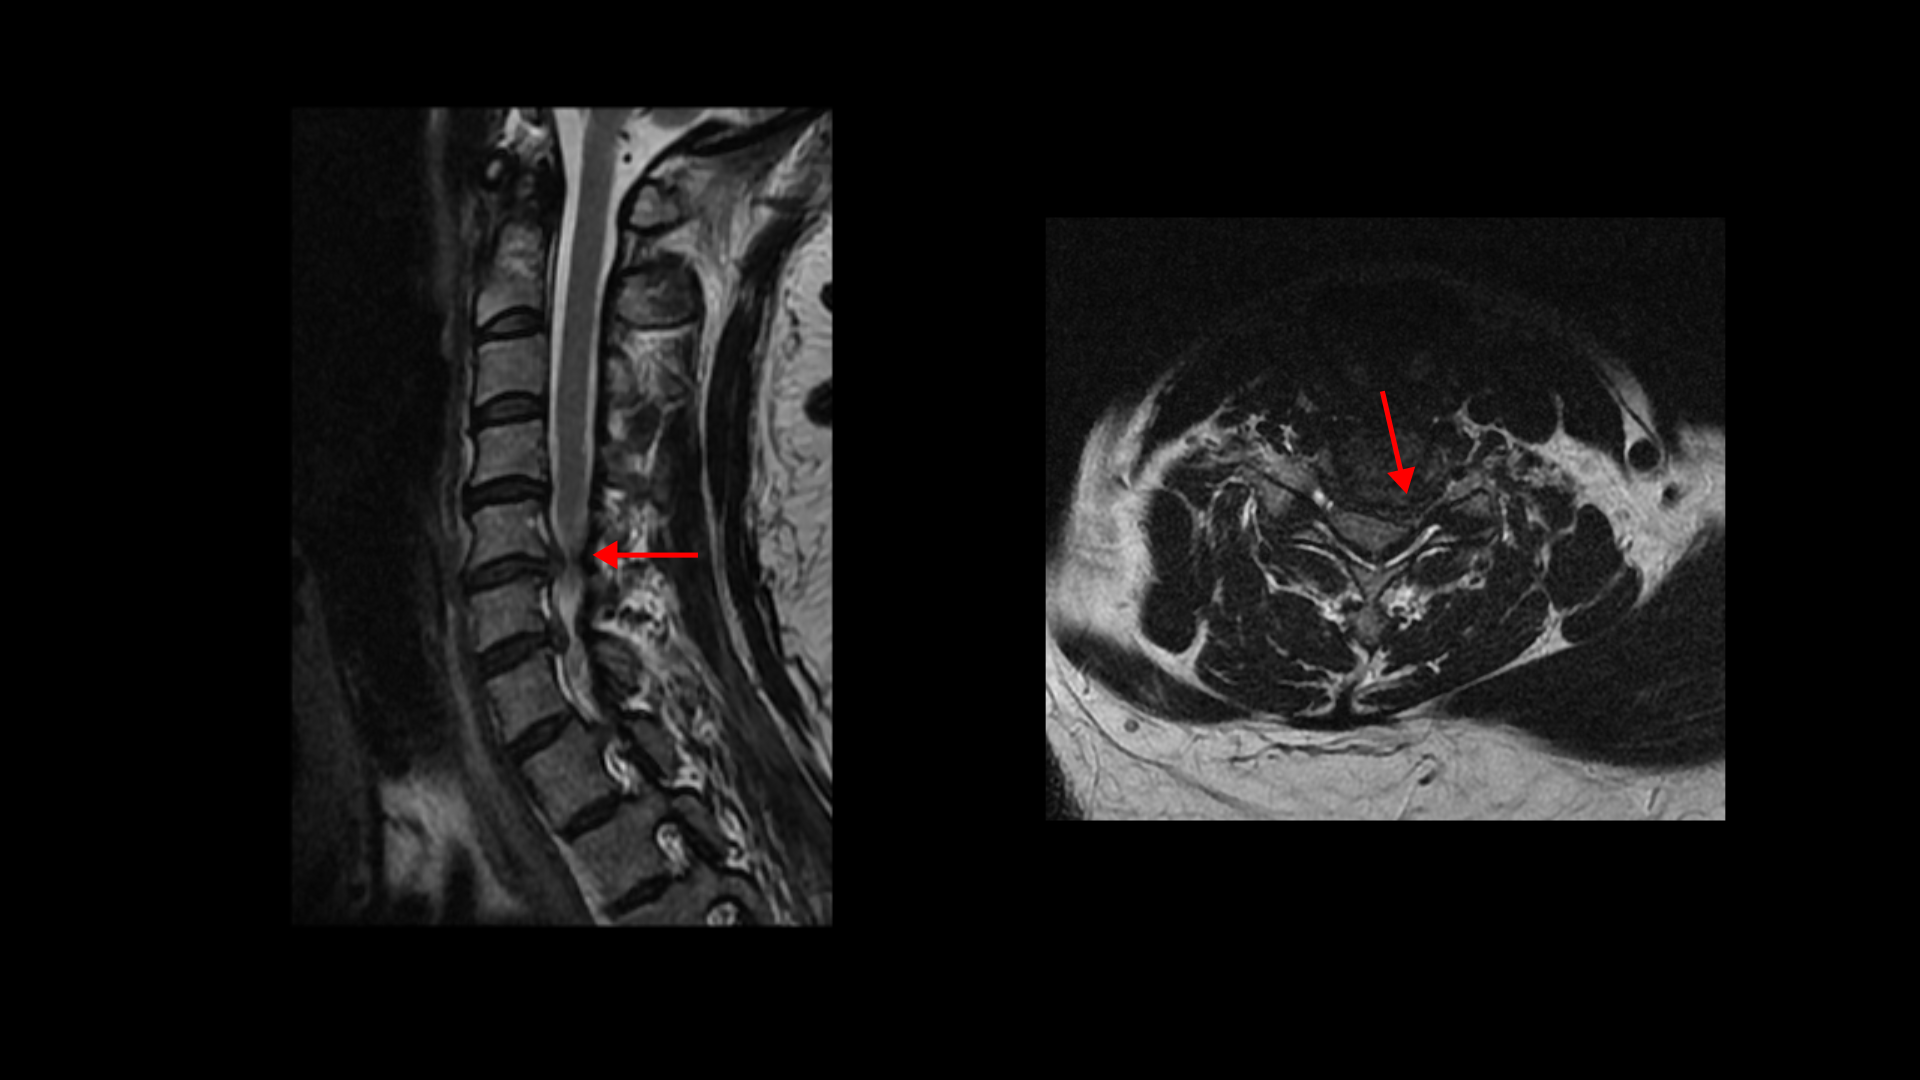

이분 MRI를 보면 목디스크 5번 6번과

6번 7번 두 마디가 왼쪽으로 심하게 밀려 나와 있습니다.

이렇게 심하게 밀려 나와 있으니까 왼쪽 팔의 통증과 함께 마비도 있고 앉거나 일어서면 목의 커브가 조금씩 변하면서 신경을 더 눌러, 앉기도 서서 걷기도 어려운 겁니다.